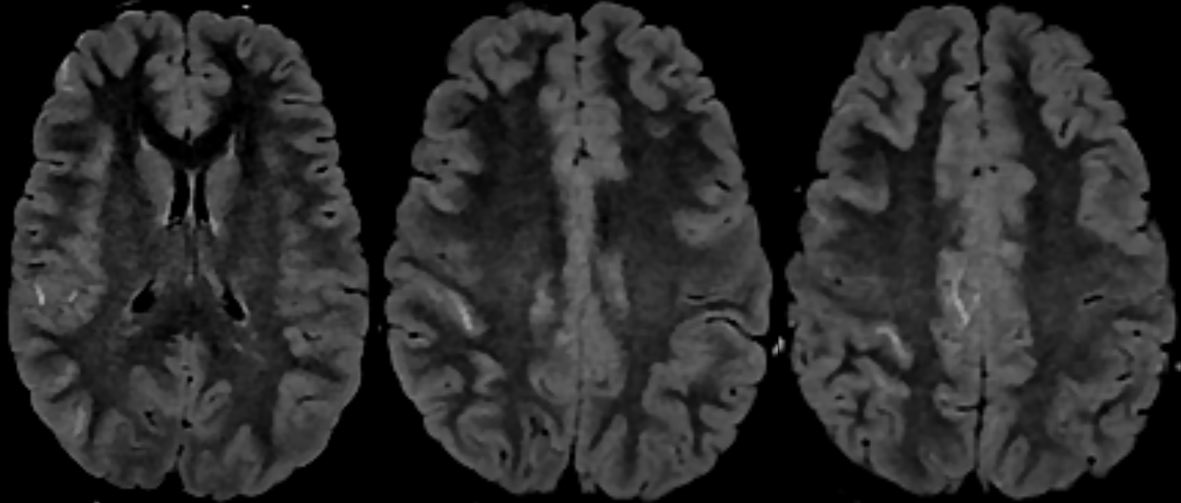

Imaging of Moyamoya disease/syndrome Imaging: Thread-like intracranial ICA/MCA with attenuated branches and “puff of smoke” appearance on DSA Co